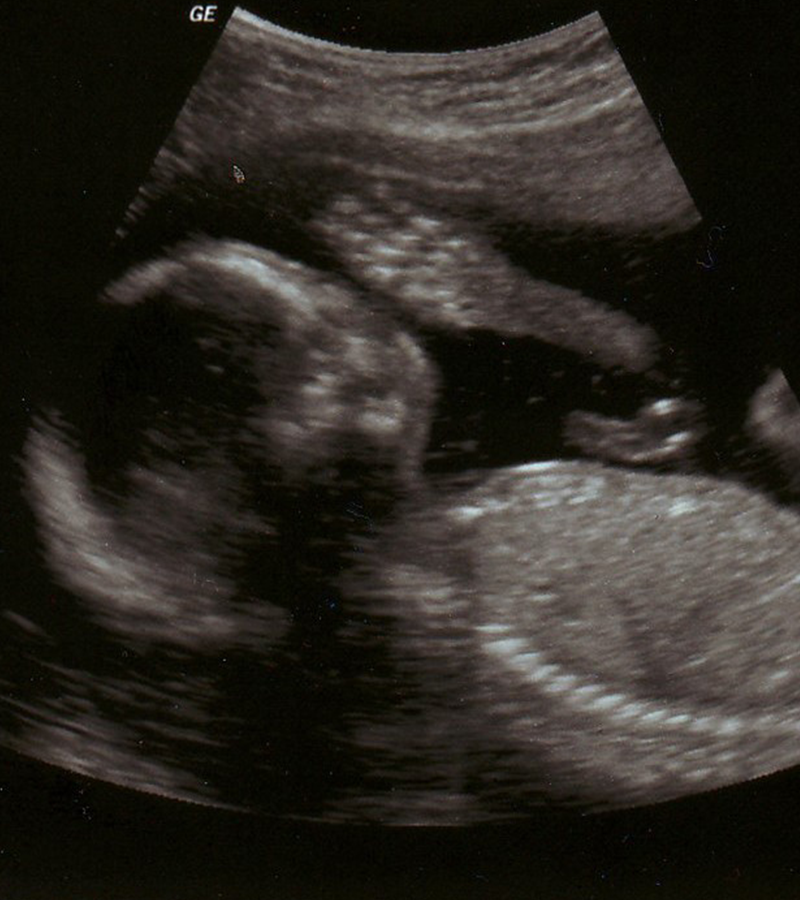

La ricerca scientifica ha evidenziato che il feto è in grado di provare sensazioni e di rispondere agli stimoli esterni, è in grado, quindi, di vedere, udire, toccare, apprendere, entrando in comunicazione con la propria madre, il proprio padre, i fratelli e tutto l’ambiente circostante. È sensibile alle sollecitazioni positive come a quelle negative, il feto memorizza queste esperienze in relazione alla graduale maturazione del suo sistema nervoso centrale, che già all’inizio del terzo trimestre di vita intrauterina raggiunge i livelli di evoluzione simili a quelli che presenterà il neonato. Di tutte queste esperienze che il feto fa in relazione all’ambiente esterno e alla madre egli ne conserverà il ricordo remoto associato a stati emotivi (Chamberlain, 1998).

Durante la veglia attiva il feto compie i movimenti respiratori, muove gli arti e la frequenza cardiaca segue un tipico andamento di accelerazione e rallentamenti in dipendenza dai rumori e dagli stati emotivi materni trasmessi dai neuro mediatori. Durante queste fasi il feto recepisce le informazioni esterne mentre nelle fasi di quiete struttura le sue esperienze e le immagazzina. L’esperienza prenatale di interazione con l’ambiente influisce sulla struttura del sistema nervoso centrale e sull’architettura del cervello in evoluzione.

L’utero non è solo la prima culla per il bambino ma è anche il suo primo vero mondo e il modo in cui lo sperimenta incide sulla formazione della sua futura personalità (Soldera, Le emozioni della vita prenatale, 2000).

Al termine della gravidanza il feto sa stabilire la sua presenza nello spazio ed è consapevole della dimensione spaziale dell’utero che lo contiene (Mancuso 2009).